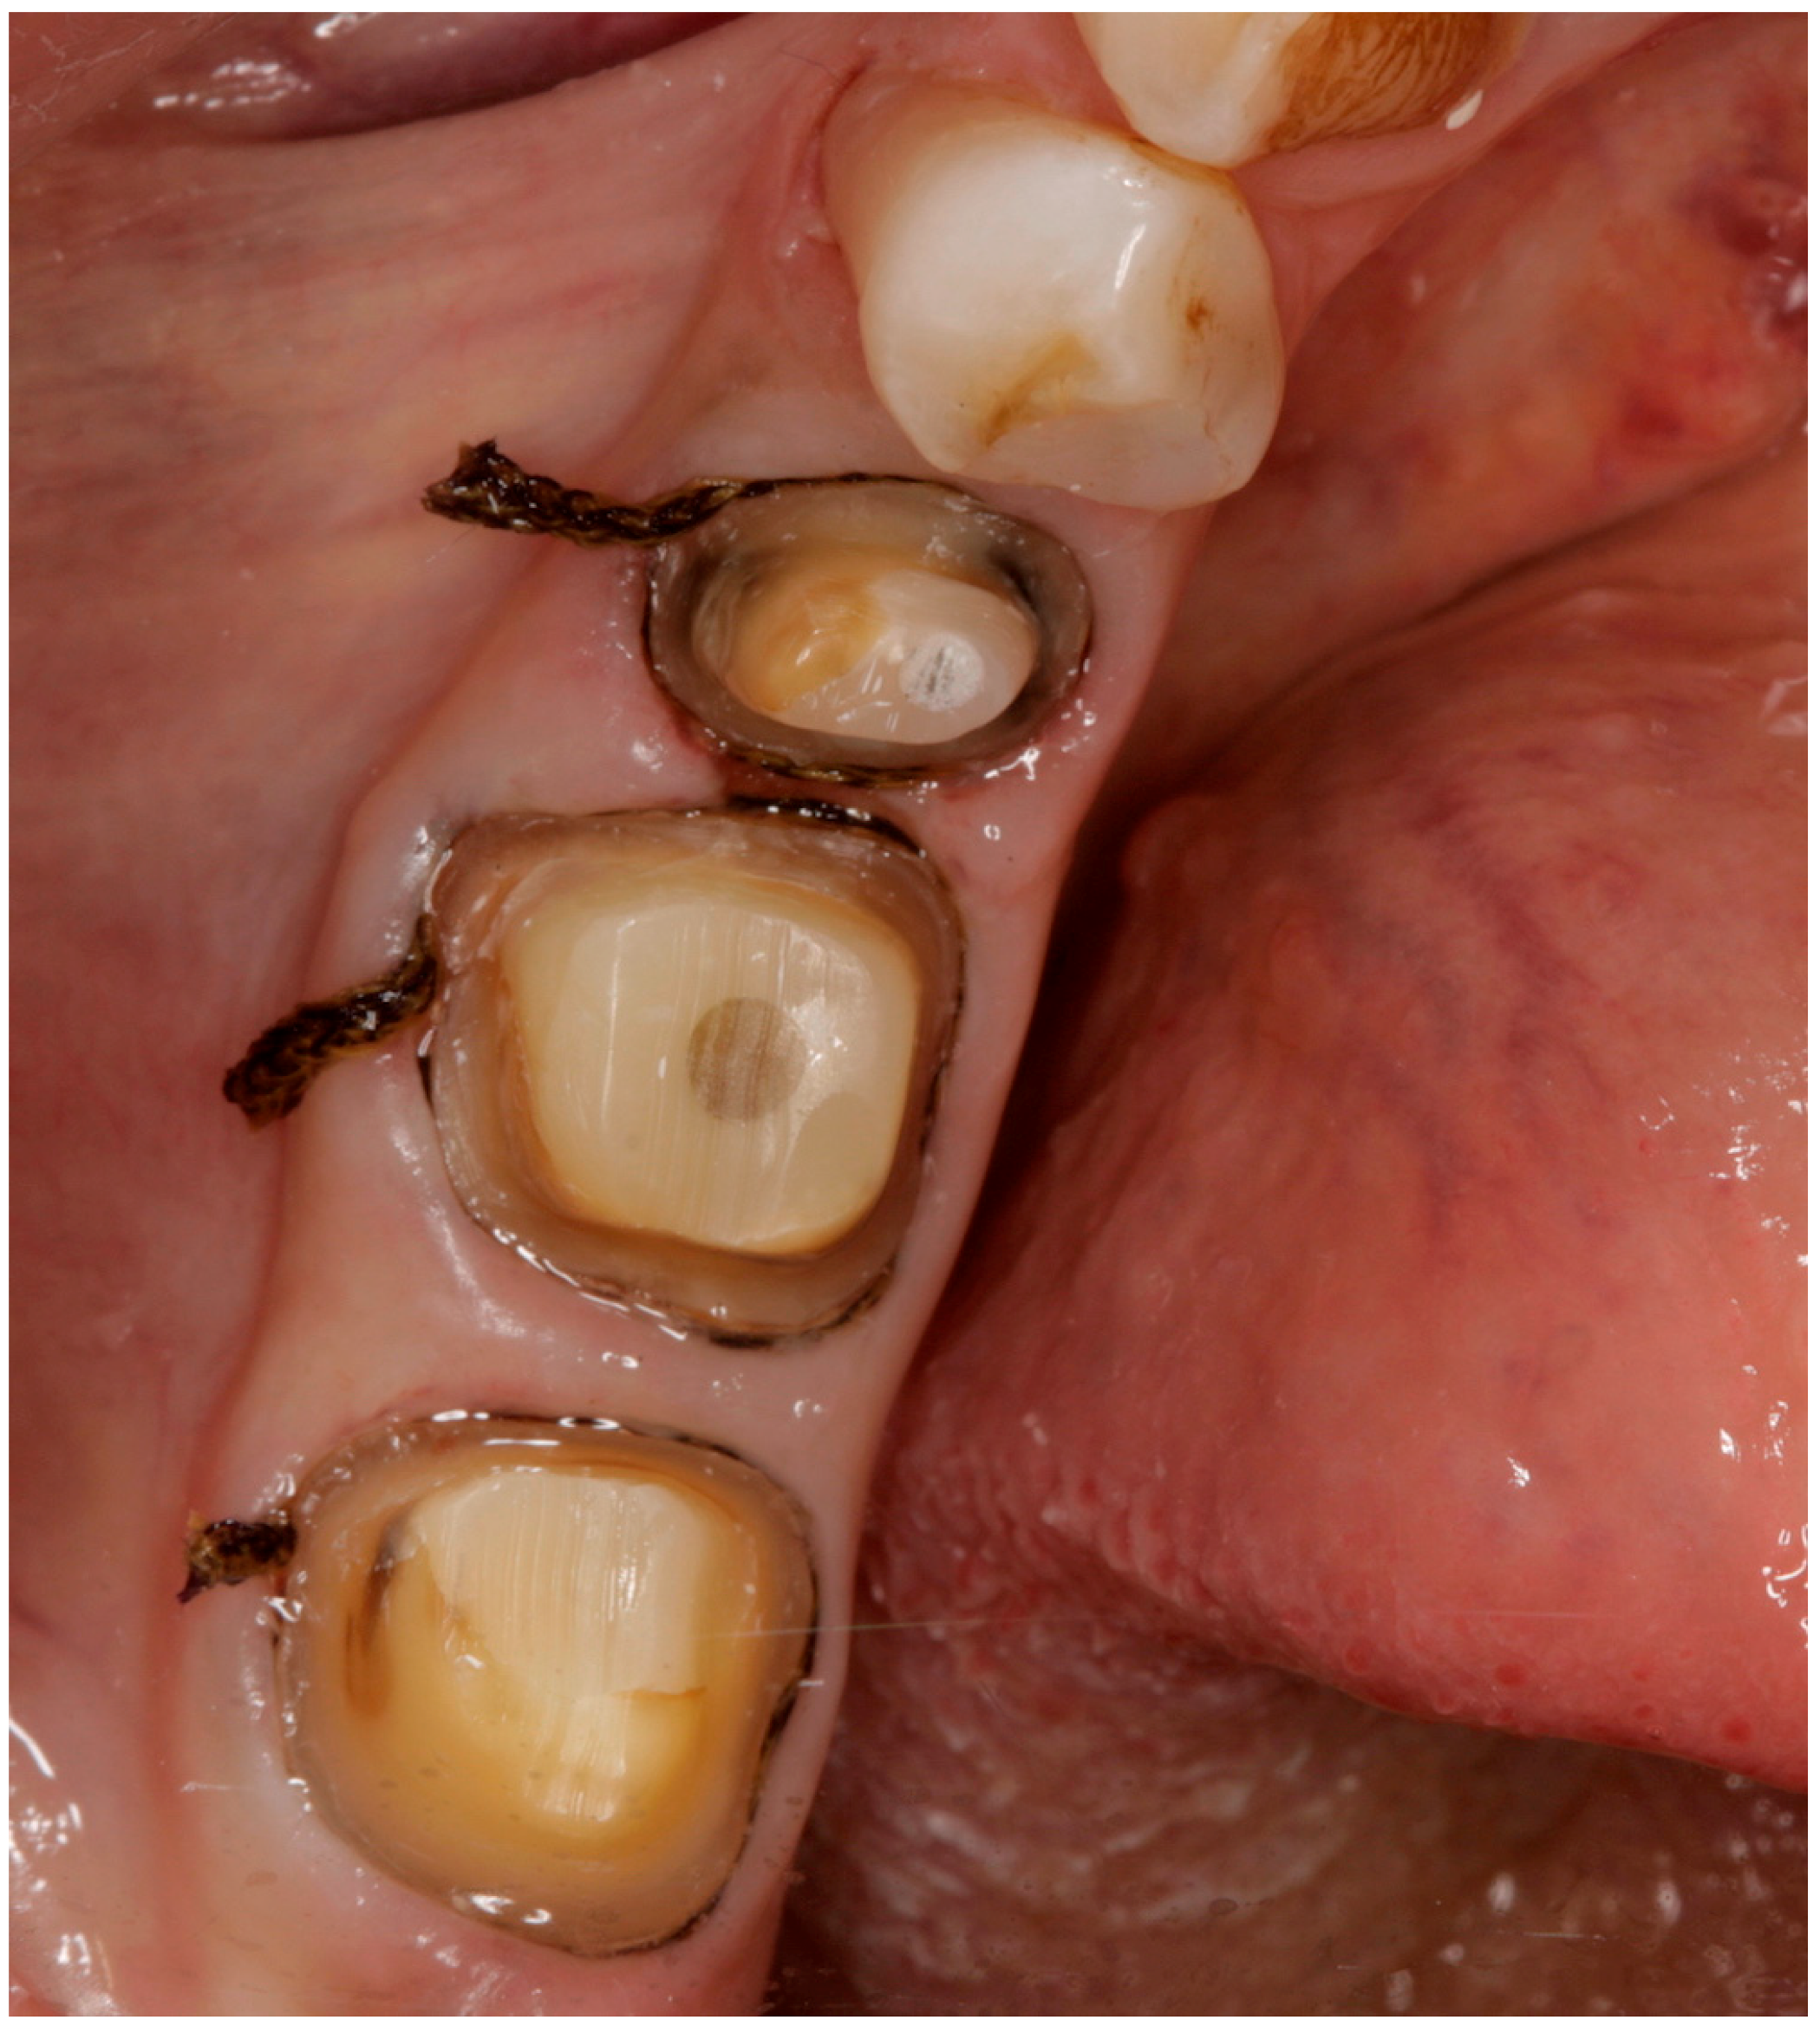

2. Materials and Methods